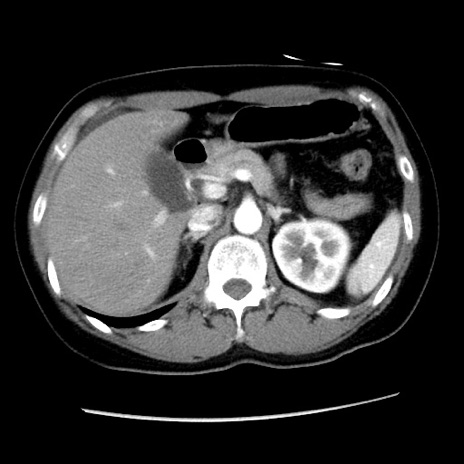

症例10(横断像)

【症例】 50歳代女性

【主訴】 腹痛

【現病歴】前日生レバーを食べた。今朝に排便あり。 昼前に突然発症の腹痛を生じ、当院救急外来を受診した。

【既往歴】 子宮筋腫にてで子宮全摘後

【身体所見】 意識清明、腹部:平坦、軟、下腹部やや左を中心に圧痛・反跳痛あり、筋性防御あり

【データ】WBC 7800、CRP 0.07